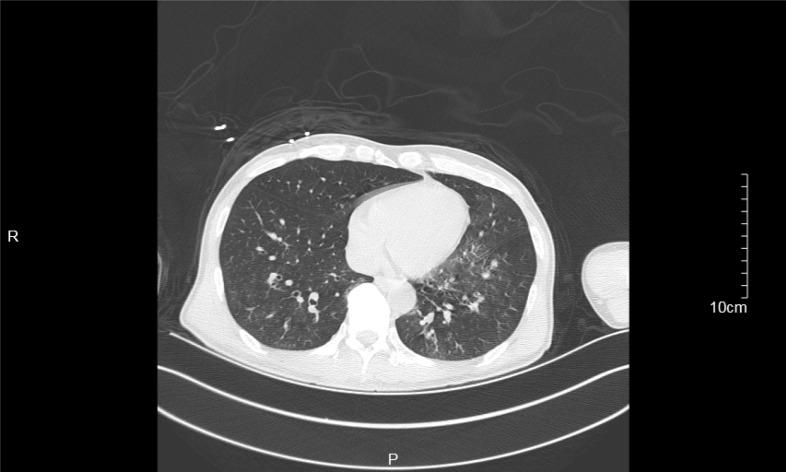

A 62-year-old Chinese man with a 40-year history of treatment-resistant schizophrenia presented to the Emergency Department with symptoms of myoclonus, consciousness disturbance and vomiting after taking 125 mg clozapine. Upon admission, the patient had a suddenly generalized tonic-clonic seizure lasting for about half a minute with persistent disturbance of consciousness, fever, cough and bloody sputum, which was considered to be low-dose clozapine-related seizure. After antiepileptic and multiple anti-infection treatments, the patient was discharged without epileptic or psychotic symptoms.

一名62岁的中国男性,有40年难治性精神分裂症病史,服用125毫克氯氮平后,因肌阵挛、意识障碍和呕吐症状就诊于急诊科。入院时,患者突然出现全身性强直 - 阵挛发作,持续约半分钟,伴有持续的意识障碍、发热、咳嗽和咯血痰,被认为是低剂量氯氮平相关的癫痫发作。经过抗癫痫和多次抗感染治疗后,患者出院时无癫痫或精神病症状。